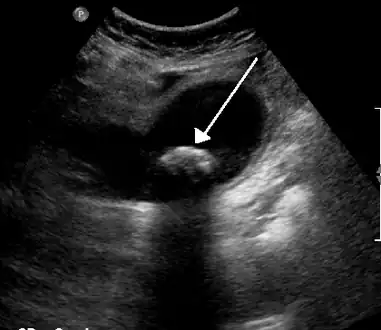

Diagnosis is typically confirmed by abdominal ultrasound. Other imaging techniques used are ERCP and MRCP. Gallstone complications may be detected on blood tests.[2]

On abdominal ultrasound, sinking gallstones usually have posterior acoustic shadowing. In floating gallstones, reverberation echoes (or comet-tail artifact) is seen instead in a clinical condition called adenomyomatosis. Another sign is wall-echo-shadow (WES) triad (or double-arc shadow) which is also characteristic of gallstones.[38]